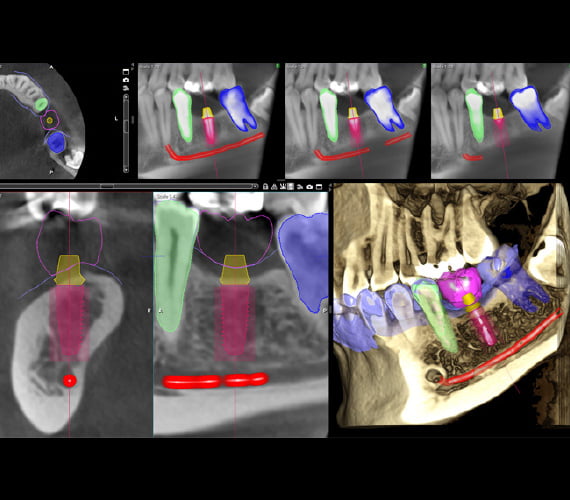

Oprogramowanie Romexis posiada bibliotekę implantów wraz z realistycznymi modelami od ponad 100 producentów. Możliwość zobaczenia środka implantu znacznie ułatwia określenie optymalnej pozycji. Ponadto oprogramowanie Romexis ostrzega użytkownika, jeśli implant znajduje się zbyt blisko sąsiadujących posegmentowanych zębów, kanału żuchwy lub innych implantów. Dostarcza również narzędzie do oceny stanu kości wokół implantu.

Planowanie implantów

Romexis jest niezbędnym oprogramowaniem do planowania w protetyce implantologicznej. Dzięki Romexis masz nieocenione możliwości pozyskiwania obrazów CBCT, skanowania powierzchni, projektowania wirtualnych koron, mapowania wszystkich uzyskanych wcześniej danych oraz realizację opracowanego planu. Oprogramowanie Romexis zapewnia również dostęp do ogólnej biblioteki koron w przypadku, gdy specjalnie zaprojektowana korona nie jest dostępna. Wartym uwagi jest również fakt, że oprogramowanie Romexis obsługuje dane DICOM oraz pliki STL, dając możliwość prostego importowania z systemów podmiotów zewnętrznych.